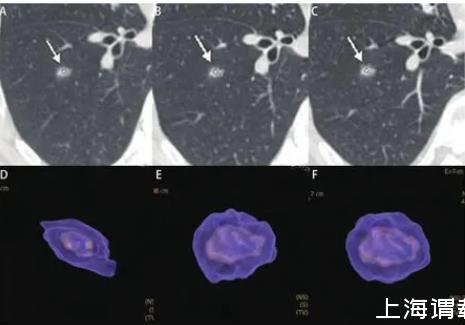

圖2男,47歲,左上葉實(shí)性結(jié)節(jié),直徑約為1.0 cm,病理為浸潤性腺癌。A、B:2013/03/12第一次CT檢查,體積為211 mm3;C、D:2013/10/10檢查,體積為235 mm3;E、F:2014/11/27檢查,體積為267 mm3。在20個(gè)月的隨訪中,結(jié)節(jié)體積無明顯增長,但術(shù)后病理診斷為腺癌。